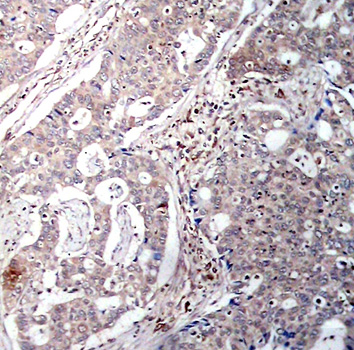

Immunohistochemical analysis of paraffin-embedded human breast carcinoma tissue using Phospho-NFKBIB-S23 antibody.